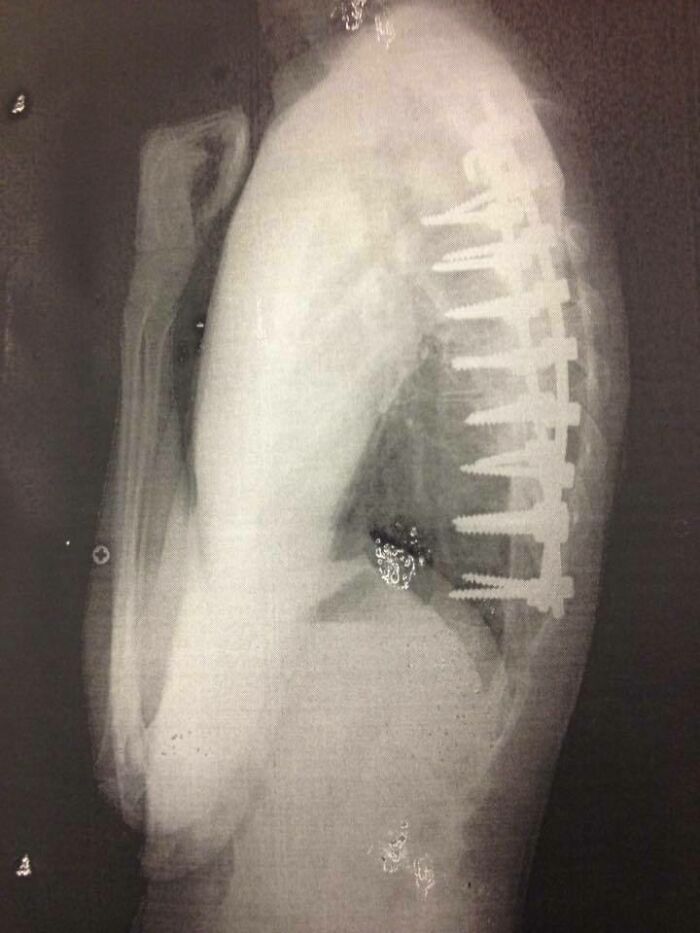

#3 Takto to vyzerá po operácii totálnej spinálnej fúzie